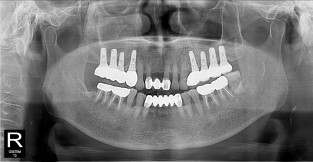

• 3

전체어금니

치료기간 : 2021-10-20 ~ 2023-08-31

1. 상기 x-ray 이미지 모두 동일한 해당 의료기관에서 진료한 환자입니다.

2. 상기 x-ray 이미지 모두 동일 인물의 것입니다.

3. 치료 전 이미지는 2021-10-20에 촬영했으며, 치료 후 이미지는 2023-08-31에 촬영하였습니다.

4. 상기 x-ray 이미지 모두 동일 조건에서 환자분의 동의를 받아촬영되었습니다.

* 임플란트 시술은 환자분의 상태(고혈압, 당뇨 등)에 따라 부작용이 있을 수 있으니, 반드시 전문의와 상담이 필요합니다.

* 임플란트 수술 부작용

: 수술 후 출혈, 교합, 통증, 붓기, 염증 등의 문제점이 발생할 수 있습니다.)